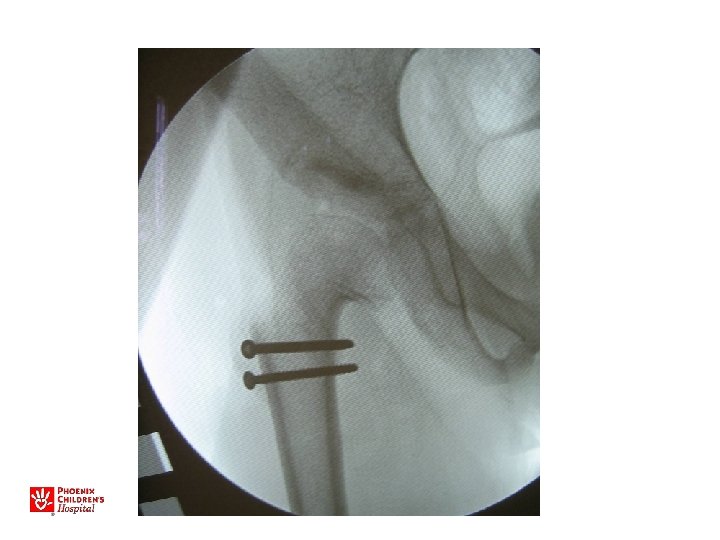

11 yo M, acute unstable SCFE

Acute, Unstable SCFE • Capsulotomy to decompress – Either anterior open approach – Capsular decompression • Open reduction – Surgical hip dislocation